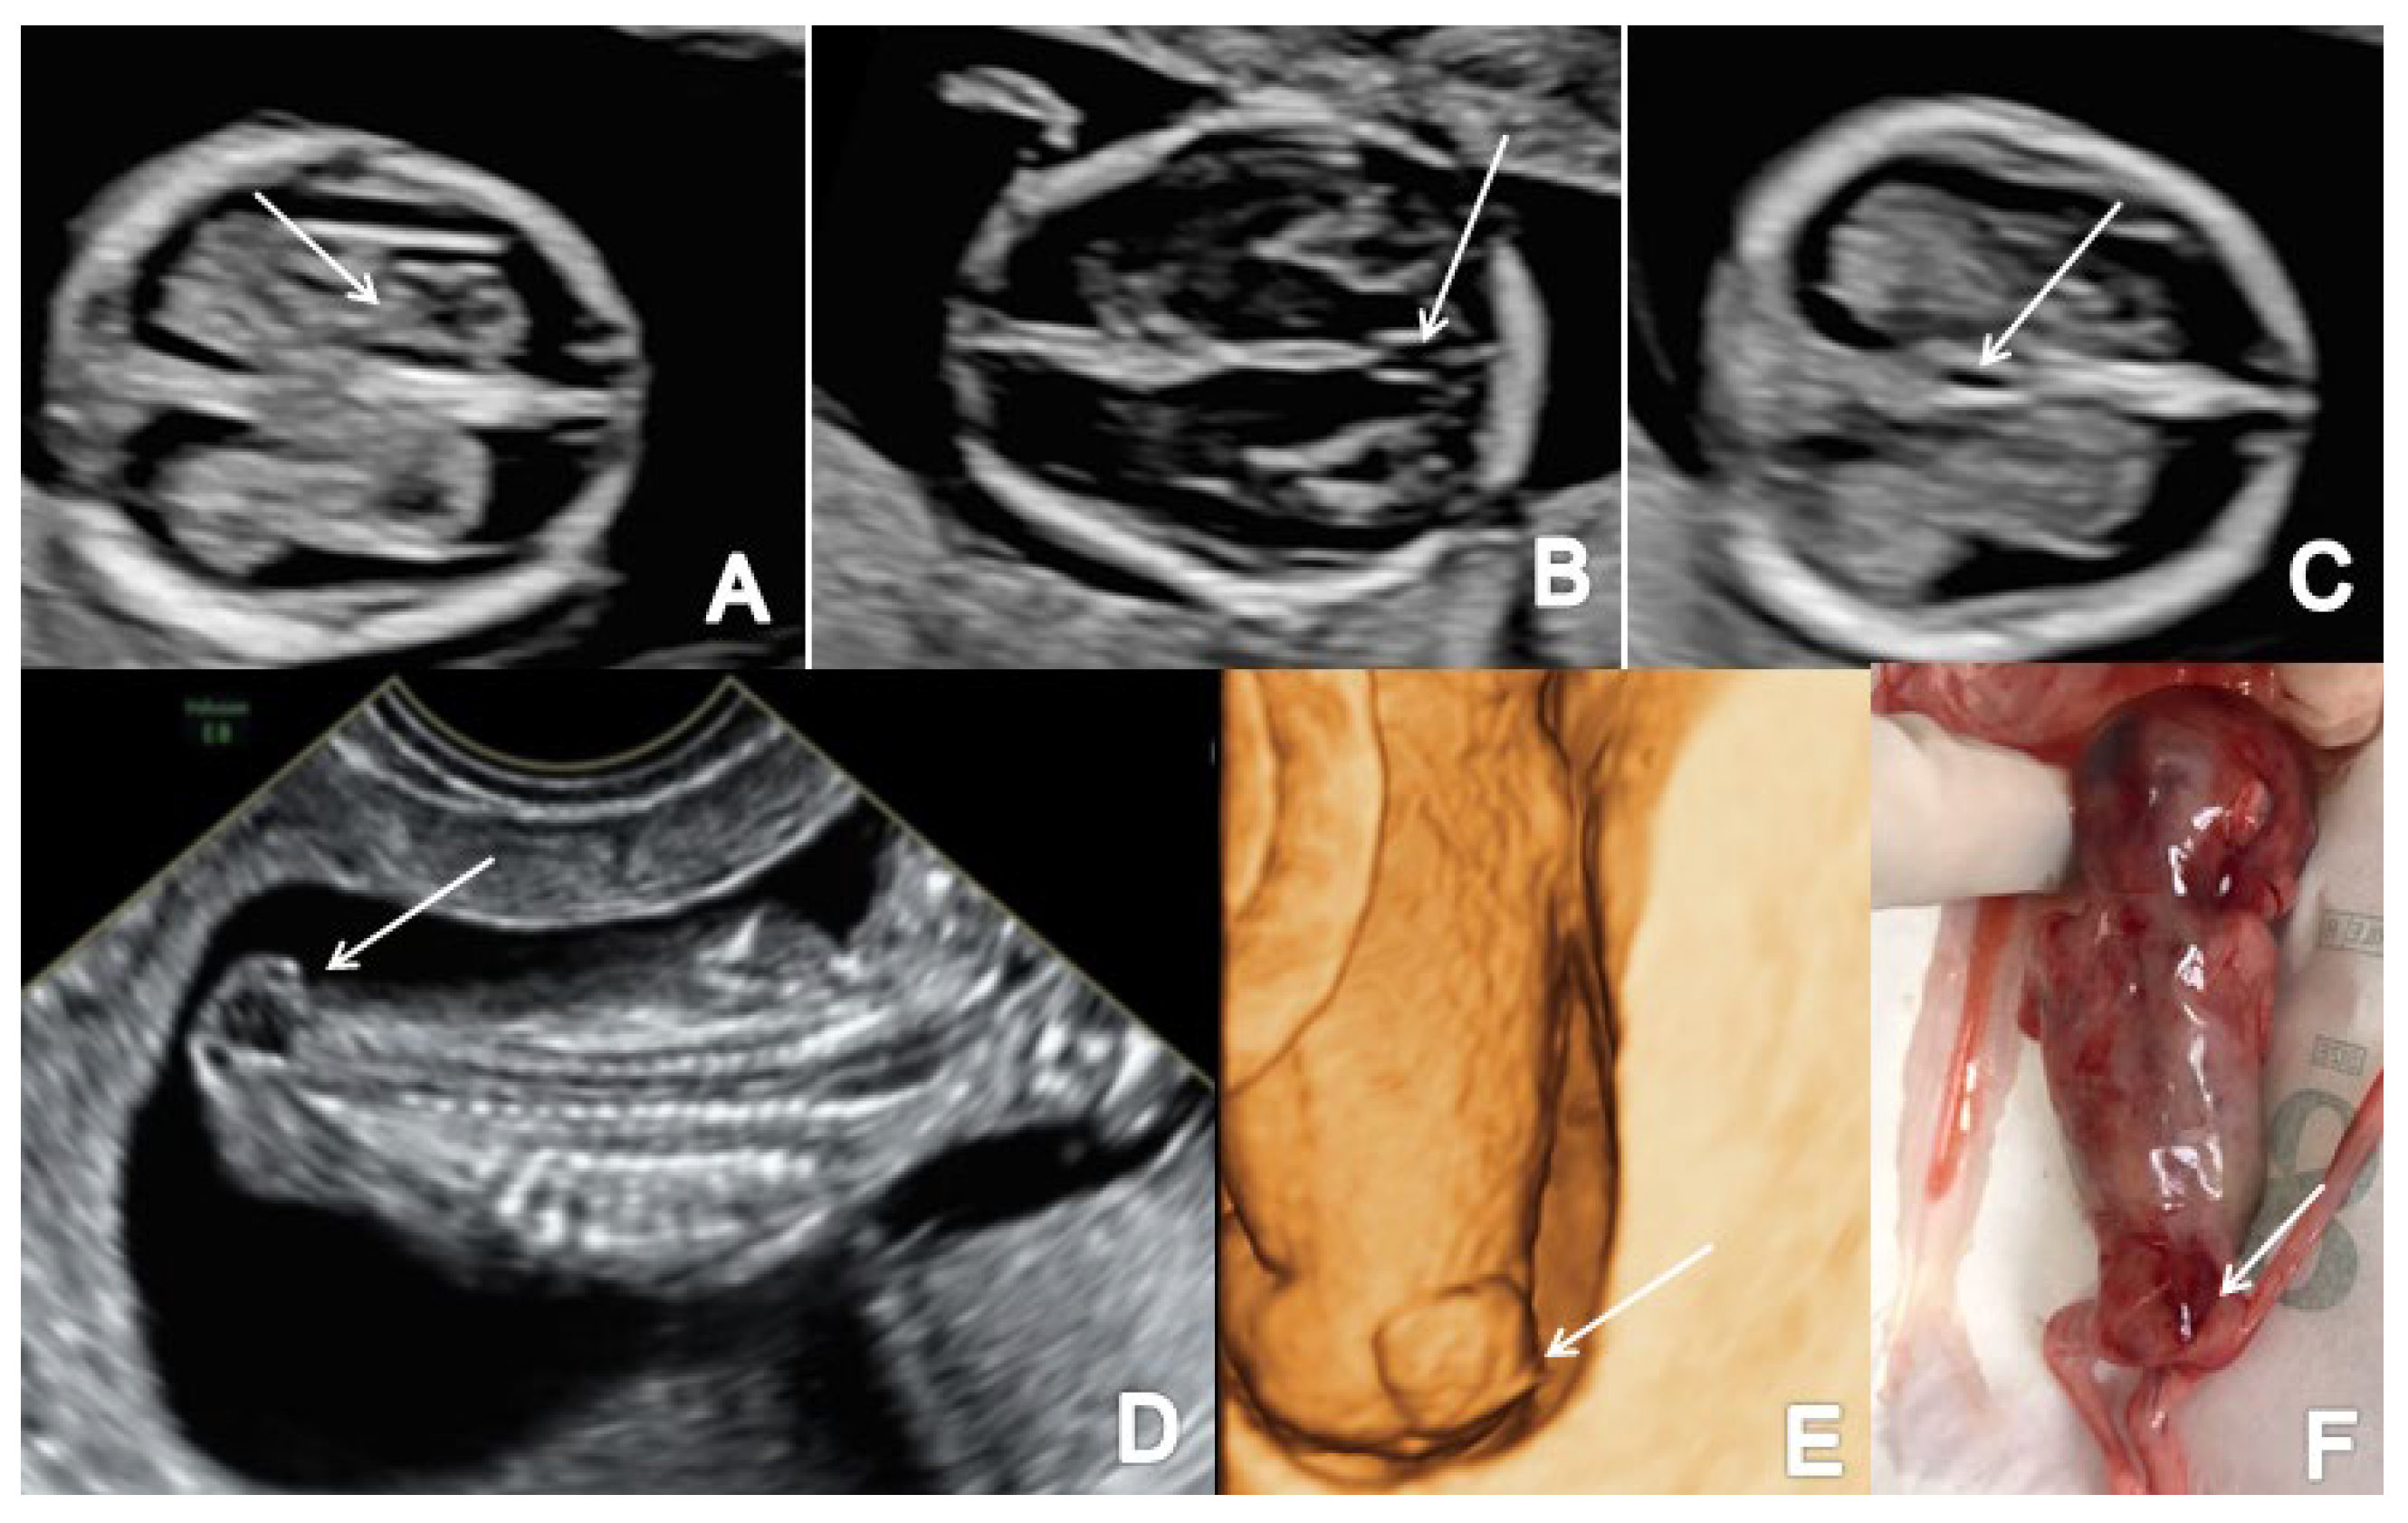

Figure 4.

A case of OSB diagnosed at 13 weeks + 2 days (Case 3): (A) transverse view of the fetal head showing normal choroid plexus (arrow) and the filling of lateral cerebral ventricles; (B,C) further evaluation of the cerebral ventricular system, in transverse planes of the brain showing the aqueduct of Sylvius (B) and the third ventricle (C) indicated by arrows; (D) sagittal view by transvaginal approach demonstrating the defect (arrow); (E,F) specimen presentation after medical TOP.

3.2. Cephalocele

The study reports two cases of cephalocele: one located in the occipital region (Figure 5) and one located in the parietal region of the fetal head. Both cases presented with an abnormal calvaria showing the cranial bone defect with a herniated fluid-filled cyst.

Figure 5.

Ultrasound image of occipital cephalocele (the arrow marks the bony defect), diagnosed at 13 weeks + 6 days (Case 13): (A) sagittal view by transvaginal approach; (B) axial view by transabdominal approach; (C,D) specimen presentation after medical TOP.